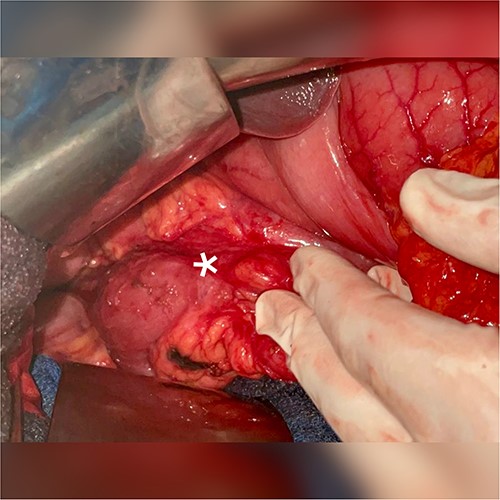

A 51-year-old patient with no significant medical history. He was admitted to the emergency department with abdominal distension, persistent vomiting, intolerance to solid foods, he could consume only small amounts of liquid. Clinical examination of the abdomen revealed diffuse tenderness in all quadrants, accompanied by severe abdominal distension. Prior to his consultation at our institution, he had undergone oesophagogastroduodenoscopy, revealing a dilated stomach and narrowing of the pyloric ring. Biopsies revealed the presence of H. pylori and S. ventriculi. (Fig. 1). He was put on conservative treatment for a duration of ~4 weeks, but no significant improvement was noted. On admission to our clinic, he underwent a computed tomography (CT) scan of the abdomen (Fig. 2), which revealed marked dilatation of the stomach, as well as an upright arrangement of the entire jejunal coves, suggesting the presence of a high occlusion due to a right anterior para-duodenal internal hernia. While a more comprehensive non-operative management approach could have been contemplated in the absence of hernia-related concerns, the clinical deterioration and the refractory nature of symptoms to medical therapy served to underscore the appropriateness of the surgical approach. During surgery, the hypothesis of a para-duodenal internal hernia was ruled out after a duodeno-pancreatic detachment using the KOCHER maneuver, thus facilitating exposure of the entire duodenum and also allowing individualization of the transition zone located at the level of the pylorus (Fig. 3), thus justifying the performance of gastroenteric anastomosis (Fig. 4). Post-operatively, the diet was progressively advanced and well tolerated. On discharge, the patient was in satisfactory condition.

1-Low magnification histological section (HE ×40) showing a bulbous mucosa housing in surface the Sarcina ventriculi germ (pin) 2-High magnification microphotograph (HE ×400) revealing the presence of cuboid-shaped germs arranged in tetrads, corresponding to Sarcina ventriculi (pin).